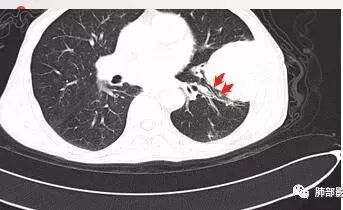

病灶与叶裂之间夹有上叶下舌段支气管、血管。舌段支气管后移,尖后段支气管前移,病灶将支气管撑开。

叶裂受压后移,提示病灶不来源于叶裂。

支气管推移-----提示外朝内

近端肺动脉受压外移,但是有部分进入病灶内-------提示与肺有千丝万缕的关系。

不符合,因为病灶的主体在肺内,而且胸膜在病灶的外侧为主

与胸膜非钝角相交

病灶的整体形态--肺内边界清晰,膨胀性为主

如果是外面长进来的,胸膜掀起的角度一般更大,呈钝角

我们换个角度讲,如果是胸壁肋骨来源,病灶外朝内生长,并且朝内生长这么大,按理说应该是内侧侵袭性强,外侧侵袭弱。但是看这个病灶,外侧边界反而不清,内侧边界清,整个形态不太符合肋骨来源,而且胸膜局部增厚也不太符合胸壁来源。我认为肋骨来源应该以肋骨为中心,偏侧可以,但不会这么明显。而且血供也不一致,应该是肋间或胸壁动脉明显。

肋骨内侧面破坏为主,朝外有轻微的推移迹象。我觉得胸壁来源的放后面,特别是支气管的堵塞,这是肺外病变很少见的,SFT也有,罕见。

综合考虑恶性肿瘤,外朝内发展,倾向于肺内来源。